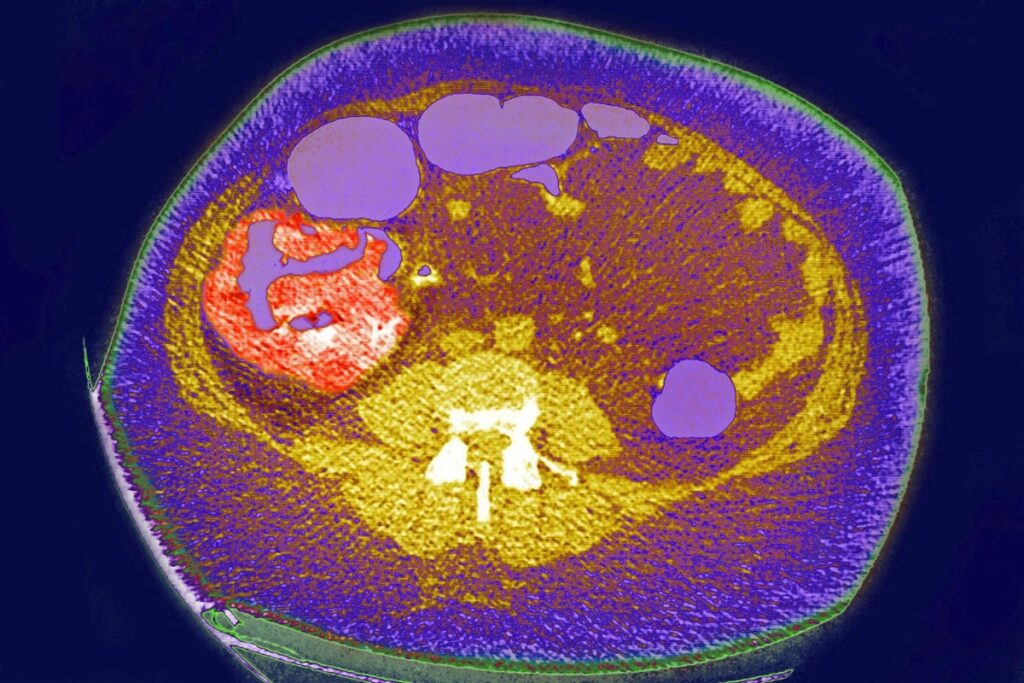

Colon cancer, tumor on the caecum and ileocolic valve, Visualization on a radial CT scan. (Photo by: … [+]